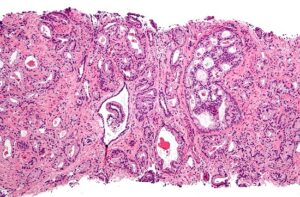

Transformen cèl·lules canceroses en innocents glòbuls blancs

Un grup d’investigadors de la Universitat de Stanford (EUA) ha aconseguit transformar cèl·lules d’un càncer [...]